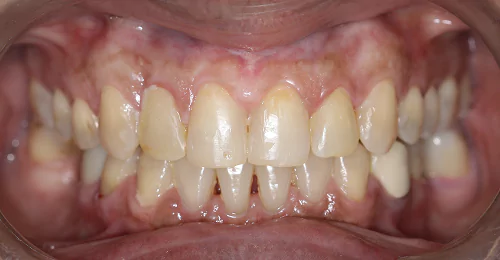

Orthodontic Case – II

(Case Done by Dr. Sonali Deshmukh M.D.S. / Orthodontist )

Correction Of Protruded

Small Lower Jaw

A child with protruded teeth and a small lower jaw at a young age can be treated by Myofunctional appliances which help in the growth of the jaw.

Pre Treatment

After Myofunctional appliances therapy for jaw growth accompanied by braces treatment for correction of protruded teeth.